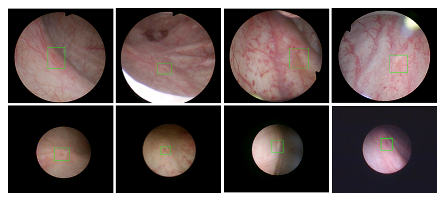

beat365在线唯一官网登录医疗机器人研究院—深睿医疗人工智能医学视频联合实验室成立于2018年7月。PI包括来自于交大生医工学院和电院的三位教授,平台建设目标是将人工智能实时地用到临床医学中去,研究方向包括:1. 建立内窥镜人工智能辅助诊断系统,通过对病灶和解剖结构的实时识别来辅助医生更好地进行微创诊断和治疗;2. 以个性化、定量化的精准诊疗技术为研发目标,重点开展医学影像智能诊断、医学可视化及计算机辅助手术规划、AI及大数据分析在临床诊疗流程中的集成应用等方向的研发。试图利用AI技术、大数据分析技术、3D打印技术、虚拟现实及增强现实技术促进临床的影像诊断、治疗方案设计、预后预测分析等诊疗环节的智能化提升与技术变革;3. 面向运动医学康复、神经退行性疾病量化诊断,以及其他与人体运动相关的疾病诊疗、康复应用,开展视觉三维人体运动的测量、分析与识别研究,通过基于深度学习的视觉检测识别以及相关大数据分析,为相关疾病的诊疗和康复提供AI辅助。具体临床应用包括:关节镜手术术后康复指导和评估、帕金森病的量化诊断、精神疾病的量化诊断与评估、儿童异常行为分析等。

近年来,联合实验室发展了泌尿镜手术实时识别技术,人体姿态精确识别技术,另外围绕小儿先心病手术、肝癌消融手术、数字口腔诊疗的智能化提升等内容进行应用研发。